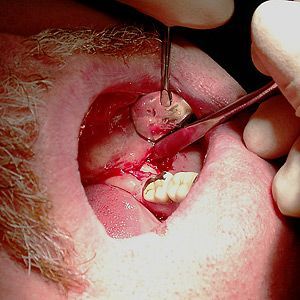

Auch bei gründlicher Inspektion des Leerkieferabschnittes im Bereich des 4. Quadranten konnte optisch kein Herd oder Störfeld ausgemacht werden. Es wurde trotzdem ein OP-Termin vereinbart, weil der Patient angab, dass er immer, wenn er über die entsprechende Zahnzone des 48. behandelt wurde, tagelang keine nennenswerten Schmerzen und Bewegungseinschränkungen mehr hatte. Dieser Test der Störfeldbeeinflussung über die entsprechenden Reflexzonen ist viermal gemacht worden, mit immer den gleichen positiven Ergebnissen. Das war der Grund, warum der Patient sich schließlich zu einer Operation entschloss.